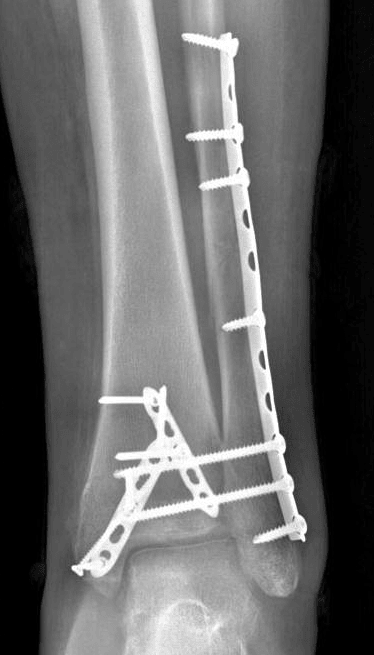

Radiograph in this patient after ORIF.